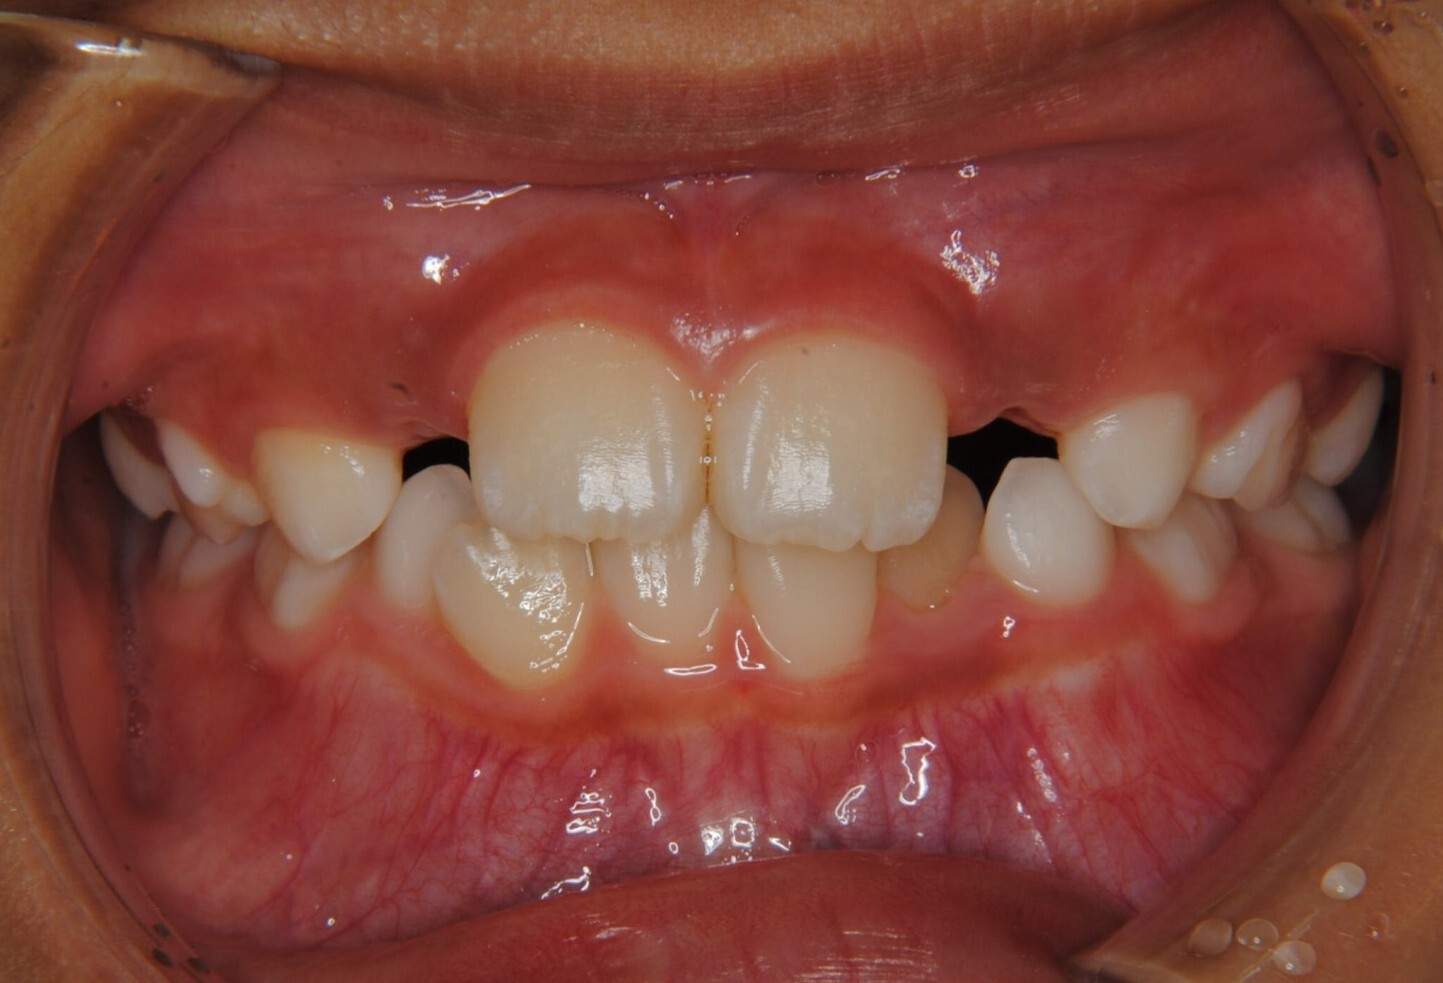

②診断名:Ⅰ級叢生

③年齢:初診時(左写真)8歳6か月、終了時(右写真)11歳4か月